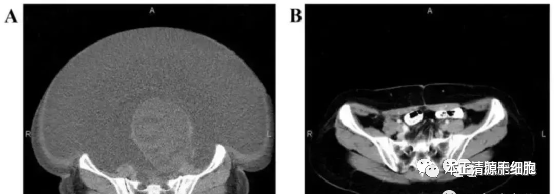

免疫治疗作为一种很有发展前途的肿瘤治疗手段,其依托于机体自身免疫系统,充分挖掘机体免疫潜能,可对肿瘤细胞进行有效抑制乃至去除。其中,自然杀伤 (NK) 细胞是一种在免疫疗法中具有巨大潜力的免疫细胞。最近,针对应用NK细胞治疗癌症的研究综述《NK Cell Therapy: A Rising Star in Cancer Treatment》发表于国际肿瘤核心期刊《Cancers》。研究发现,癌症组织中的 NK 细胞数量低于正常水平,这种情况下有助于癌细胞的生长。另外,NK细胞免疫功能损害,对抗癌免疫有干扰作用。因此正开展大量研究来发展基于提高NK细胞数目、提高NK细胞活性和解除肿瘤微环境中NK细胞抑制作用的癌症治疗策略已成为一个主流研究领域。NK细胞,全名“自然杀伤细胞”(Natural Killer cell,NK),是在核心的细胞军团中与T、B细胞并列的第三类群淋巴细胞。NK细胞较大,含有胞浆颗粒,故称大颗粒淋巴细胞。NK细胞杀伤的靶细胞主要是肿瘤细胞、病毒感染细胞、较大的病原体(如真菌和寄生虫)等。 MD安德森癌症中心的免疫治疗专家Katy Rezvani说,“NK细胞是集功效、安全性和相对易用性为一体的理想细胞疗法。”在面对癌细胞时,NK细胞不需要其他细胞的激活与刺激,便能直接识别并杀死癌细胞。 第一,这是人体内固有的免疫系统,NK细胞不需要预激活就能通过穿孔素及颗粒酶的释放对异常细胞进行识别及杀灭;第二,具有广谱的抗肿瘤作用,不需要肿瘤特异性识别,且不会被细胞表面的主要组织相容性复合体(MHC)抑制活性限制。启动时间最快,而T细胞则需要经过抗原提呈之后才能分清“敌我”;第三,情况反馈及时,一旦发现“敌情”,迅速“上报”并启动整个免疫系统的免疫防御和免疫杀伤功能。NK细胞通过多种途径来起到抗癌的作用,主要过程包括:NK细胞被招募到肿瘤微环境(TME)——NK细胞识别肿瘤并激活——杀伤局部和散在的肿瘤细胞——NK细胞协助适应性免疫应答。 然而,在肿瘤微环境(TME)中,免疫抑制细胞和细胞因子抑制 NK 细胞功能。此外,功能失调的NK细胞又可对其他抗癌过程造成不良影响,从而形成恶性循环。对NK细胞抑制状态机制的认识,将有助于治疗靶点的明确。NK 细胞对于抗癌免疫至关重要。肿瘤微环境(TME)中许多抑制因子的存在已被证明可以抑制 NK 细胞的功能。 NK细胞可以从多种来源产生,包括外周血(PB)、脐带血 (UCB)、NK 细胞系和诱导多能干细胞 (iPSC)。NK 细胞的体外扩增和功能增强,这也是十分关键的一步。 此外,NK 细胞可以在体外进行修饰以表达 CAR,从而使 NK 细胞能够识别特定的肿瘤相关抗原 (TAA),从而提高 NK 细胞疗法的靶向性和疗效。 具有免疫调节作用的细胞因子对于维持 NK 细胞的存活、增殖和成熟至关重要。 癌细胞通过细胞间接触或外泌体分泌靶向免疫细胞上表达的免疫检查点,从而抑制抗癌免疫。据文献报告病例显示,我国首例卵巢癌NK细胞患者60岁,2015年诊断晚期,伴大量腹水及巨大肿瘤时,经体外扩增、高度激活同种异体NK细胞治疗,CA125水平由11,270下降到580,腹水全部消失。此外,CT扫描的肿块体积减小,并且没有出现副作用。一项临床的观察显示:晚期肺癌患者通过了NK细胞的治疗之后疾病得以稳定的控制,实验证明了NK细胞免疫疗法可作为过继性疗法应用于晚期肺癌患者的治疗当中。实验背景:旨在探讨高度激活NK(HANK)细胞免疫疗法在晚期肺癌患者之中的疗效。入组13名患者(8名男性,5名女性)其中的中位年龄为57.3岁,诊断为腺癌(n = 12)和鳞状细胞癌(n = 1)。这些患者中,分别在 10、2 和 1 名患者当中检测到了 IV.、III.和 II. 期的患者。使用方法:入组的患者至少接受一个疗程(每个疗程包括三次的输注,每次输注的时间长度在30分钟以内)。其中每月接受治疗不超过三个疗程。每个疗程连续输注三次,并持续3天(大约3-5×109每天将NK细胞收集到输血袋之中,以约2×10的浓度进行输注7/mL)。在治疗以前与最后一次输注后测量淋巴细胞亚群,细胞因子产生以及癌胚抗原(CEA)与胸苷激酶1(TK1)的表达。实验结果:发现没有观察到明显副作用。经过了3个月的随访,病情开始稳定进展的患者比例分别为84.6%和15.4%。除此之外,治疗后IFN-γ水平有明显升高,CEA水平大幅下降。其中接受了NK细胞治疗的患者整体的免疫功能保持稳定。大量研究数据表明,NK细胞疗法在提高恶性肿瘤患者免疫功能和生存质量方面都有极为不错的表现。根据2022年新发布的全球细胞疗法,我们不难发现NK细胞疗法可能成为CAR-T疗法后细胞免疫疗法下一个主角,今后它一定会被更多地用于防癌抗癌方面,也可望为更多的病人提供一种全新的选择。